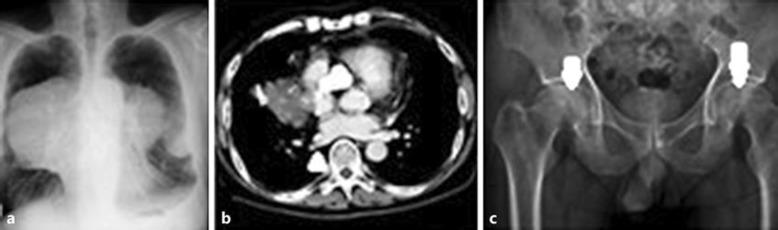

We report 2 cases of patients with solid tumors and coagulopathy who experienced avascular necrosis (AVN) of the bone following chemotherapy. Both cases exhibited nontraumatic bilateral AVN of the femoral heads, and one also showed bilateral AVN of the humeral heads. One case had multiple thromboembolic complications, including pulmonary obstructive syndrome and paraneoplastic pain. The other showed multiple paraneoplastic syndromes, with hypercalcemia and thrombocytosis. Groin pain and claudication of the lower extremities developed and persisted. Both patients eventually received bilateral hip arthroplasty due to AVN of both femoral heads.